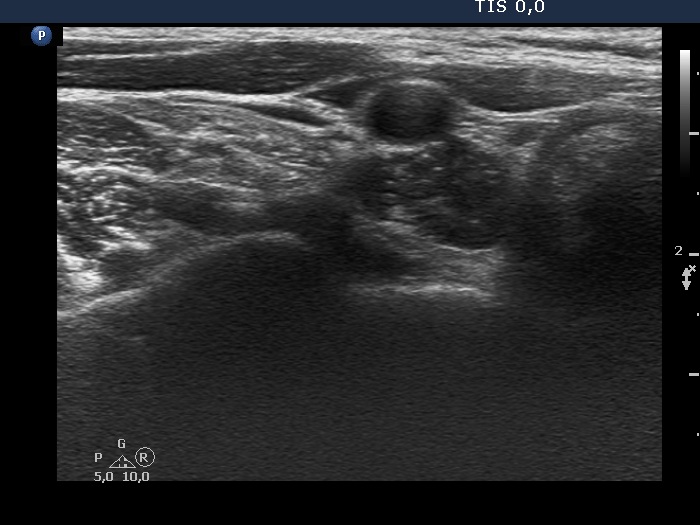

Ultrasound. Connective tissue replaced the thyroid parenchyma in both thyroid beds. There was a hypoechoic mass in the lower part of the right thyroid bed dorsal to the carotid artery. The lesion was a mixed, dominantly solid nodule and had microcalcifications.